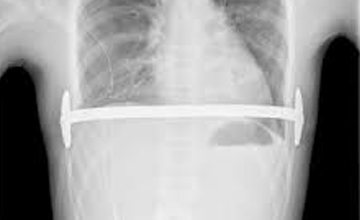

VAKUM TEDAVİSİ - Ameliyatsız Yöntem

VAKUM TEDAVİSİ

Ameliyatsız Yöntem

Pektus ekskavatumun tedavisinde seçilmiş bir grup hastada uygulanan vakum (vacuum bell) tedavisi ...